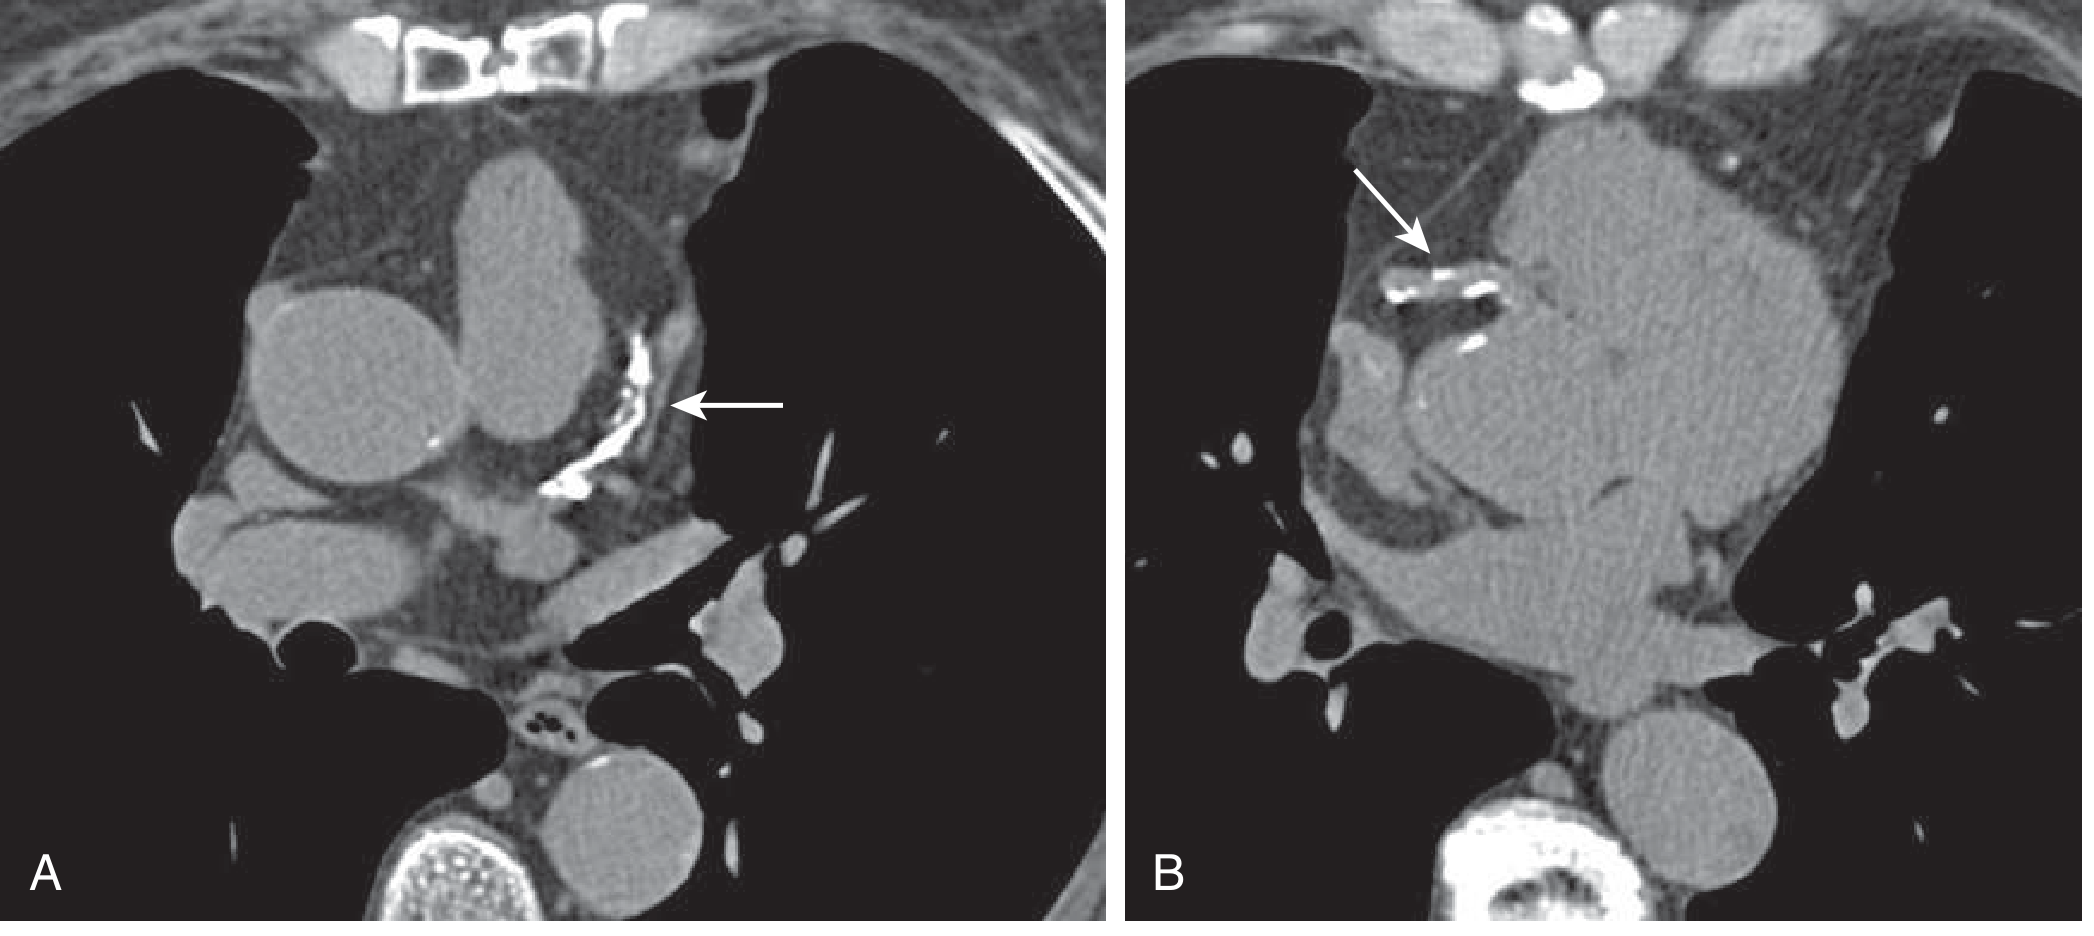

Non-Contrast CT: Example Images

Non-contrast CT axial slices for coronary calcium scoring. A: Proximal LAD with extensive calcification (arrow). B: Proximal RCA with spotty calcification (arrow). This patient's Agatston score was 457.

Non-contrast CT axial slices for calcium scoring. A: Proximal LAD with extensive calcification. B: Proximal RCA with spotty calcification. CAC score = 457 — Goldman-Cecil Medicine, p. 452